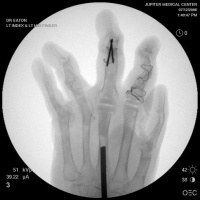

Clinical Example: Rheumatoid reconstruction with metacarpal head bone graft to recreate proximal phalanx dorsal cortex for silastic MCP arthroplasty

Rheumatoid arthritis commonly affects the hands in a variety of ways. Although more effective medications have lessened the number of patients requiring reconstruction for rheumatoid hand deformities, surgery is needed for some cases. This case demonstrates MCP arthroplasty using bone graft from the metacarpal head to recreate the dorsal cortex of the proximal phalanx lost from chronic subluxation.

This woman has undergone multiple rheumatoid procedures elsewhere. On the right, these included right wrist fusion and MCP silicone arthroplasties. On the left, silicone arthroplaties of the thumb MCP, index and middle PIP joints and arthrodesis of the thumb IP, ring and small PIP koints. She wanted improvement of her left hand function, which was hindered by wrist pain and flail fingers.

Xrays show radiocarpal collapse, proximal migration of the proximal phalanges, flail PIP joints and loss of the proximal half of the dorsal cortex of the proximal phalanges.